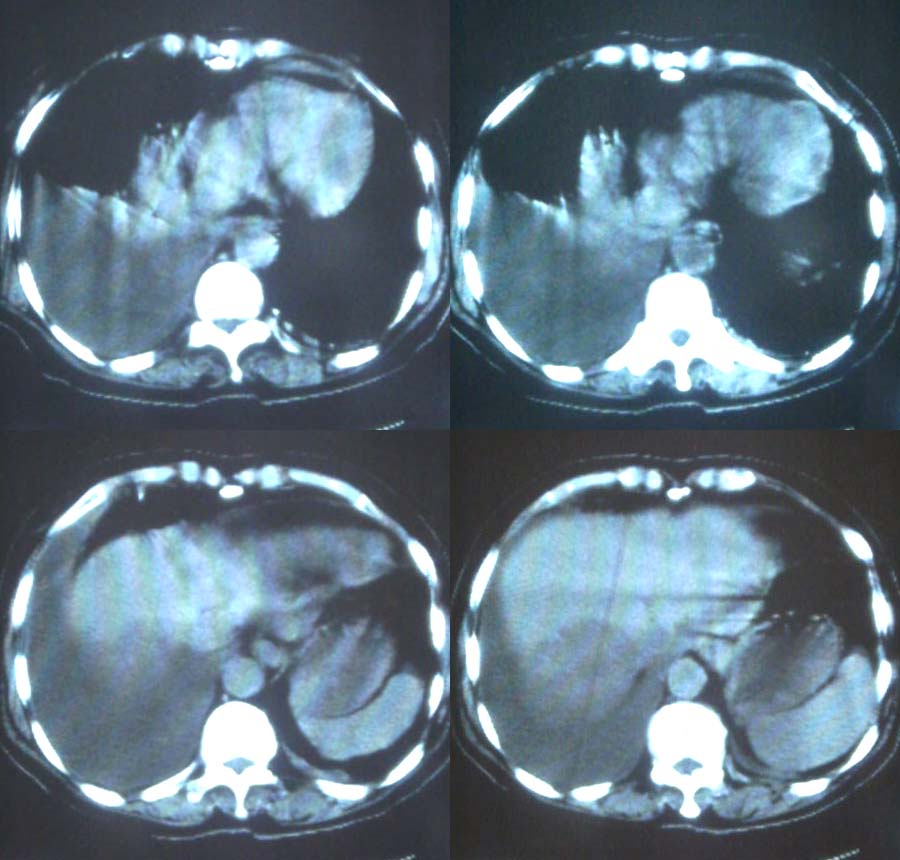

这是一个75岁女性患者,右下腹痛。胸透示,右下肺可见大片状高密度影,右侧胸腔积液。请各位老师帮忙看看腹腔都有什么病变,谢谢!

右侧中心型肺癌伴大量胸腔积液、肝转移、右肾上腺转移。

考虑:1、肝、右侧肾上腺转移瘤;

2、右侧大量胸腔积液伴下叶肺不张;

3、建议进一步检查胸部找原发灶。

1、分析:(1)女性75岁;(2)单侧大量胸腔积液;(3)右侧肺门区团块影,单纯的压迫性肺不张?肿块?;(4)肝脏内多发结节影,大小不等,多结节型肝癌?肝癌并肝脏内转移?(5)肝脏内结节病灶中心有更低密度区;(6)右侧肾上腺不规则软组织灶;(7)肝脏各叶比例正常,脾脏不大。

2、诊断:肺癌肝脏、肾上腺转移并右侧胸腔积液。应该没问题吧?